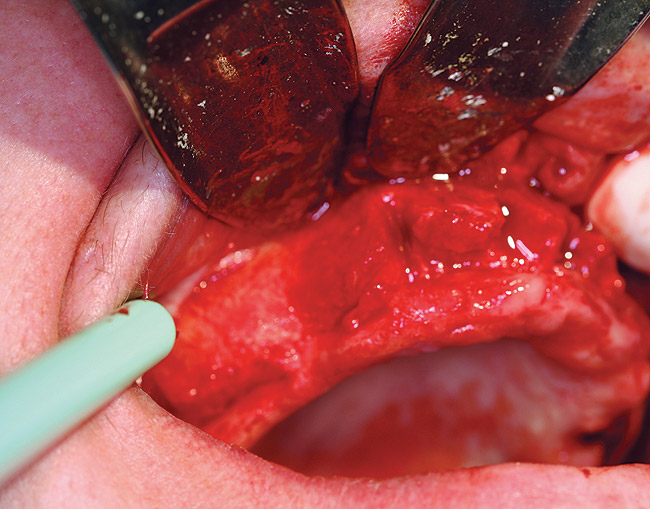

A 56-year-old woman in good health presented with recent extractions and a fully edentulous maxillary arch and edentulous posterior mandibular areas. A CBCT scan 3D view revealed large osseous defects in the maxillary arch that required grafting before implant placement (Figure 1). The treatment plan was made for maxillary ridge augmentation followed by fixed prosthesis-supported dental implants in all of the edentulous areas. The mandible did not require grafting. The patient was wearing a full upper denture during the entire grafting and subsequent implant healing time period. The maxillary arch showed large defects on the axial view of the CBCT (Figure 2). A cross-sectional CBCT view also showed deficient height of bone with a vertical height of 9.7 mm (Figure 3). Upon full-thickness reflection, large deficient areas of the ridge were seen that required grafting before implant placement (Figure 4).

Figure 4  Clinical view of osseous defects after full-thickness reflection.

Figure 4

A 53-year-old woman in good health presented for the replacement of missing teeth on the maxillary arch and periodontal therapy of the mandibular arch. A CBCT scan was taken that revealed the need for bone grafting on the maxillary ridge and maxillary sinus areas in the panographic (Figure 14) and axial (Figure 15) views. Bone loss was noted on the facial plate areas of the anterior ridge. A treatment plan was created to graft the maxillary ridge and sinuses bilaterally, and then to place 12 dental implants to support a fixed prosthesis on the maxillary arch.The treatment plan for the mandible consisted of periodontal surgery to save her remaining teeth.

Figure 16  Clinical view after full-thickness reflection showing osseous defects.

Figure 16